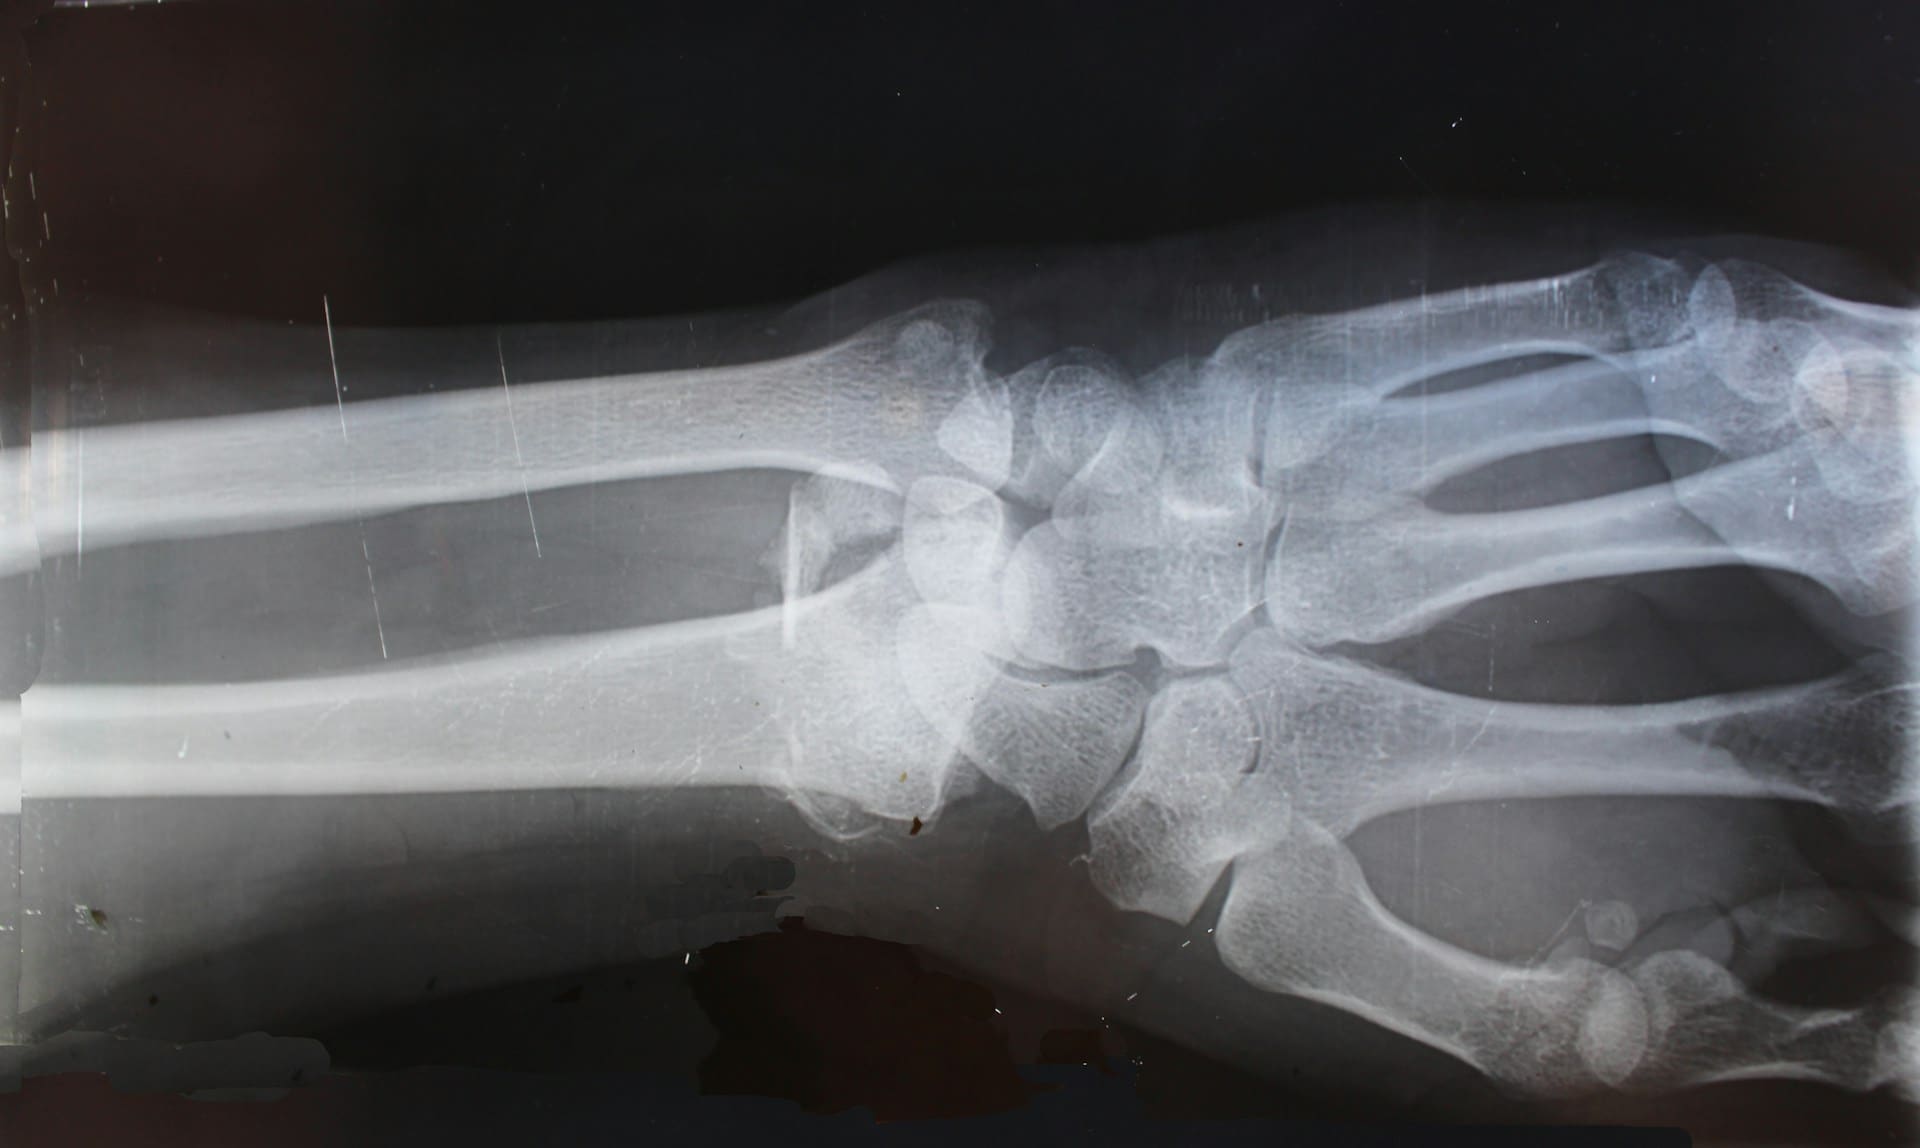

- Animal model: in rabbits with femoral defects too large to heal on their own, comparing the printed bone grafts to commercial bone cement.

Over a 12-week period, the printed grafts showed:

- Better bone regeneration with a more natural structure.

- Higher bone surface area and cortical thickness (indicators of strength).

- No signs of inflammation or necrosis in surrounding tissues.